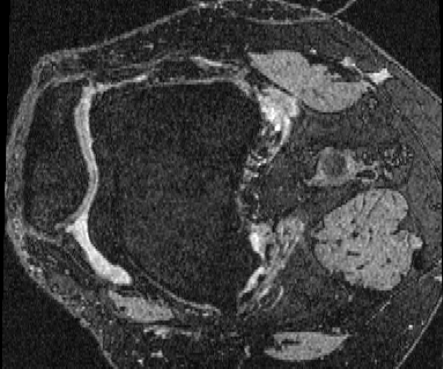

OAI Knee MRI We train and test on the split published with [22], with 2532 training examples and 301 test pairs from the Osteoarthritis Initiative (OAI) [16]444https://nda.nih.gov/oai. We evaluate using the mean Dice score of tibial and fibial cartilage. To compare directly to [22, 7, 23] we train and evaluate at [80x192x192].

| Moving Image | Warped Image | Fixed Image | Moving Image | Warped Image | Fixed Image |